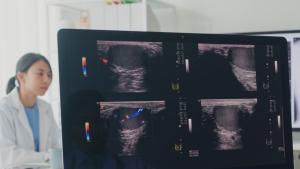

Китайски екип е разработил първия в страната универсален модел на

...... на рак на пикочния мехур. Този напредък може значително да намали работното натоварване на диагностиците и да повиши ефективността на прегледа на медицински изображения, заявиха изследователите.

Китайски екип е разработил първия в страната универсален модел на

...... пикочния мехур. Този напредък може значително да намали работното натоварване на диагностиците и да повиши ефективността на прегледа на медицински изображения, заявиха изследователите, цитирани от Синхуа.

Китайски екип е разработил първия в страната универсален модел на

...... мехур. Този напредък може значително да намали работното натоварване на диагностиците и да повиши ефективността на прегледа на медицински изображения, заявиха изследователите, цитирани от Синхуа.

Китайски екип е разработил първия в страната универсален модел на

...... пикочния мехур. Този напредък може значително да намали работното натоварване на диагностиците и да повиши ефективността на прегледа на медицински изображения, заявиха изследователите, цитирани от Синхуа.

Китайски екип е разработил първия в страната универсален модел на

...... пикочния мехур. Този напредък може значително да намали работното натоварване на диагностиците и да повиши ефективността на прегледа на медицински изображения, заявиха изследователите, цитирани от Синхуа.

Китайски екип е разработил първия в страната универсален модел на

...... на прегледа на медицински изображения, заявиха изследователите, цитирани от Синхуа.Всеки момент е важен! Последвайте ни в и , за да сте в крак с темите на деня

Китайски екип е разработил първия в страната универсален модел на

...... мехур. Този напредък може значително да намали работното натоварване на диагностиците и да повиши ефективността на прегледа на медицински изображения, заявиха изследователите, цитирани от Синхуа.